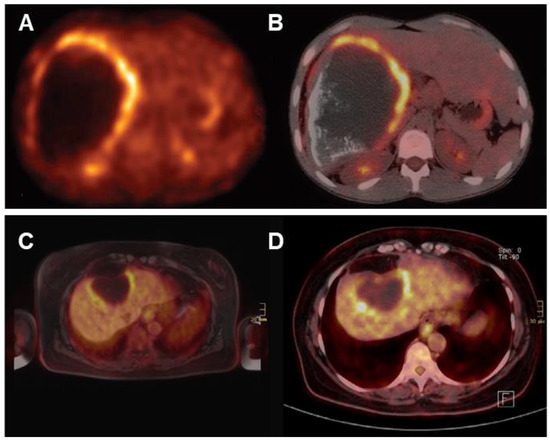

Understanding the typical manifestations of HAE in diagnostic imaging may facilitate early diagnosis. Kratzer et al. [90] established a detailed sonomorphological classification based on a large sample of patients with confirmed hepatic AE, which is mainly divided into the following five patterns (Figure 4): (A) Hailstorm: ill-defined and irregular borders, uneven patterns, and high echogenicity formation; (B) Pseudocystic: a pseudocystic appearance resulting from central necrosis, surrounded by an irregular, ring-shaped area of high echogenicity; (C) Hemangioma-like: a relatively well-demarcated, heterogeneous tumor that appears hyperechoic compared to the surrounding liver parenchyma; (D) Ossification: isolated or clustered lesions, mostly with well-defined borders, accompanied by dorsal acoustic shadow; (E) Metastasis-like: mostly hypoechoic without the halo phenomenon, featuring a central, heterogeneous, hyperechoic scar. Sulima et al. [91] analyzed the ultrasound results of 58 patients with a possible or confirmed diagnosis of AE and found that the most common patterns of AE lesions in the liver were the Hailstorm and Pseudocystic patterns. They also found that there was no correlation between the clinical stage of the disease and the ultrasonographic appearance of lesions, and specific ultrasound patterns of lesions cannot determine the radicality of surgical treatment.